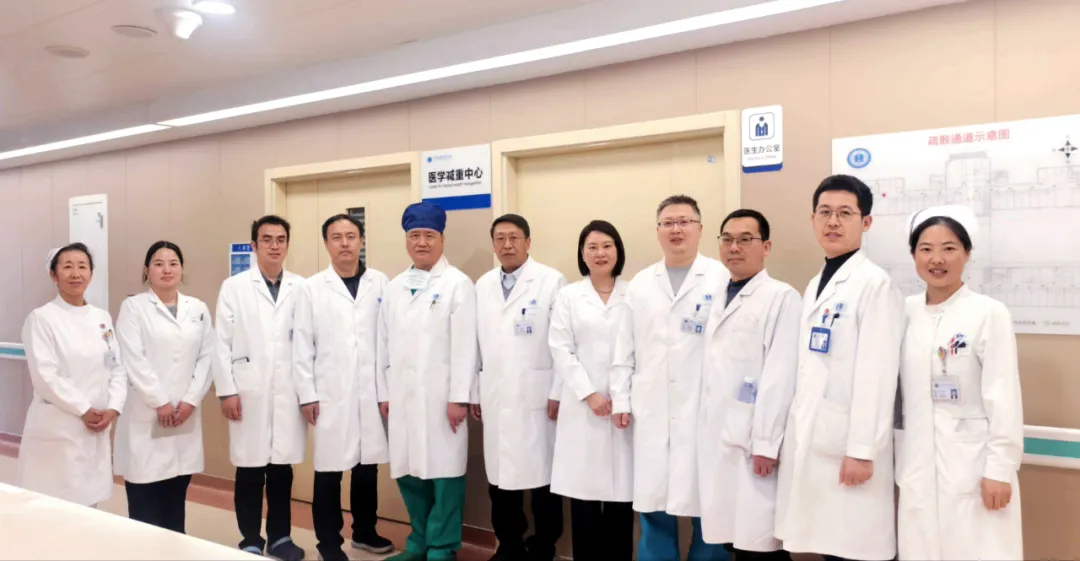

多学科协作赋能肥胖诊疗 | 我院医学减重中心举办公开参访活动

近日,我院医学减重中心成功举办了首场参访活动。活动通过多个环节的系统展示,让来自省内多地的医疗专家深入了解了体重管理的标准化流程与多学科协作模式。 环节一:门诊与病房实地观摩 ...